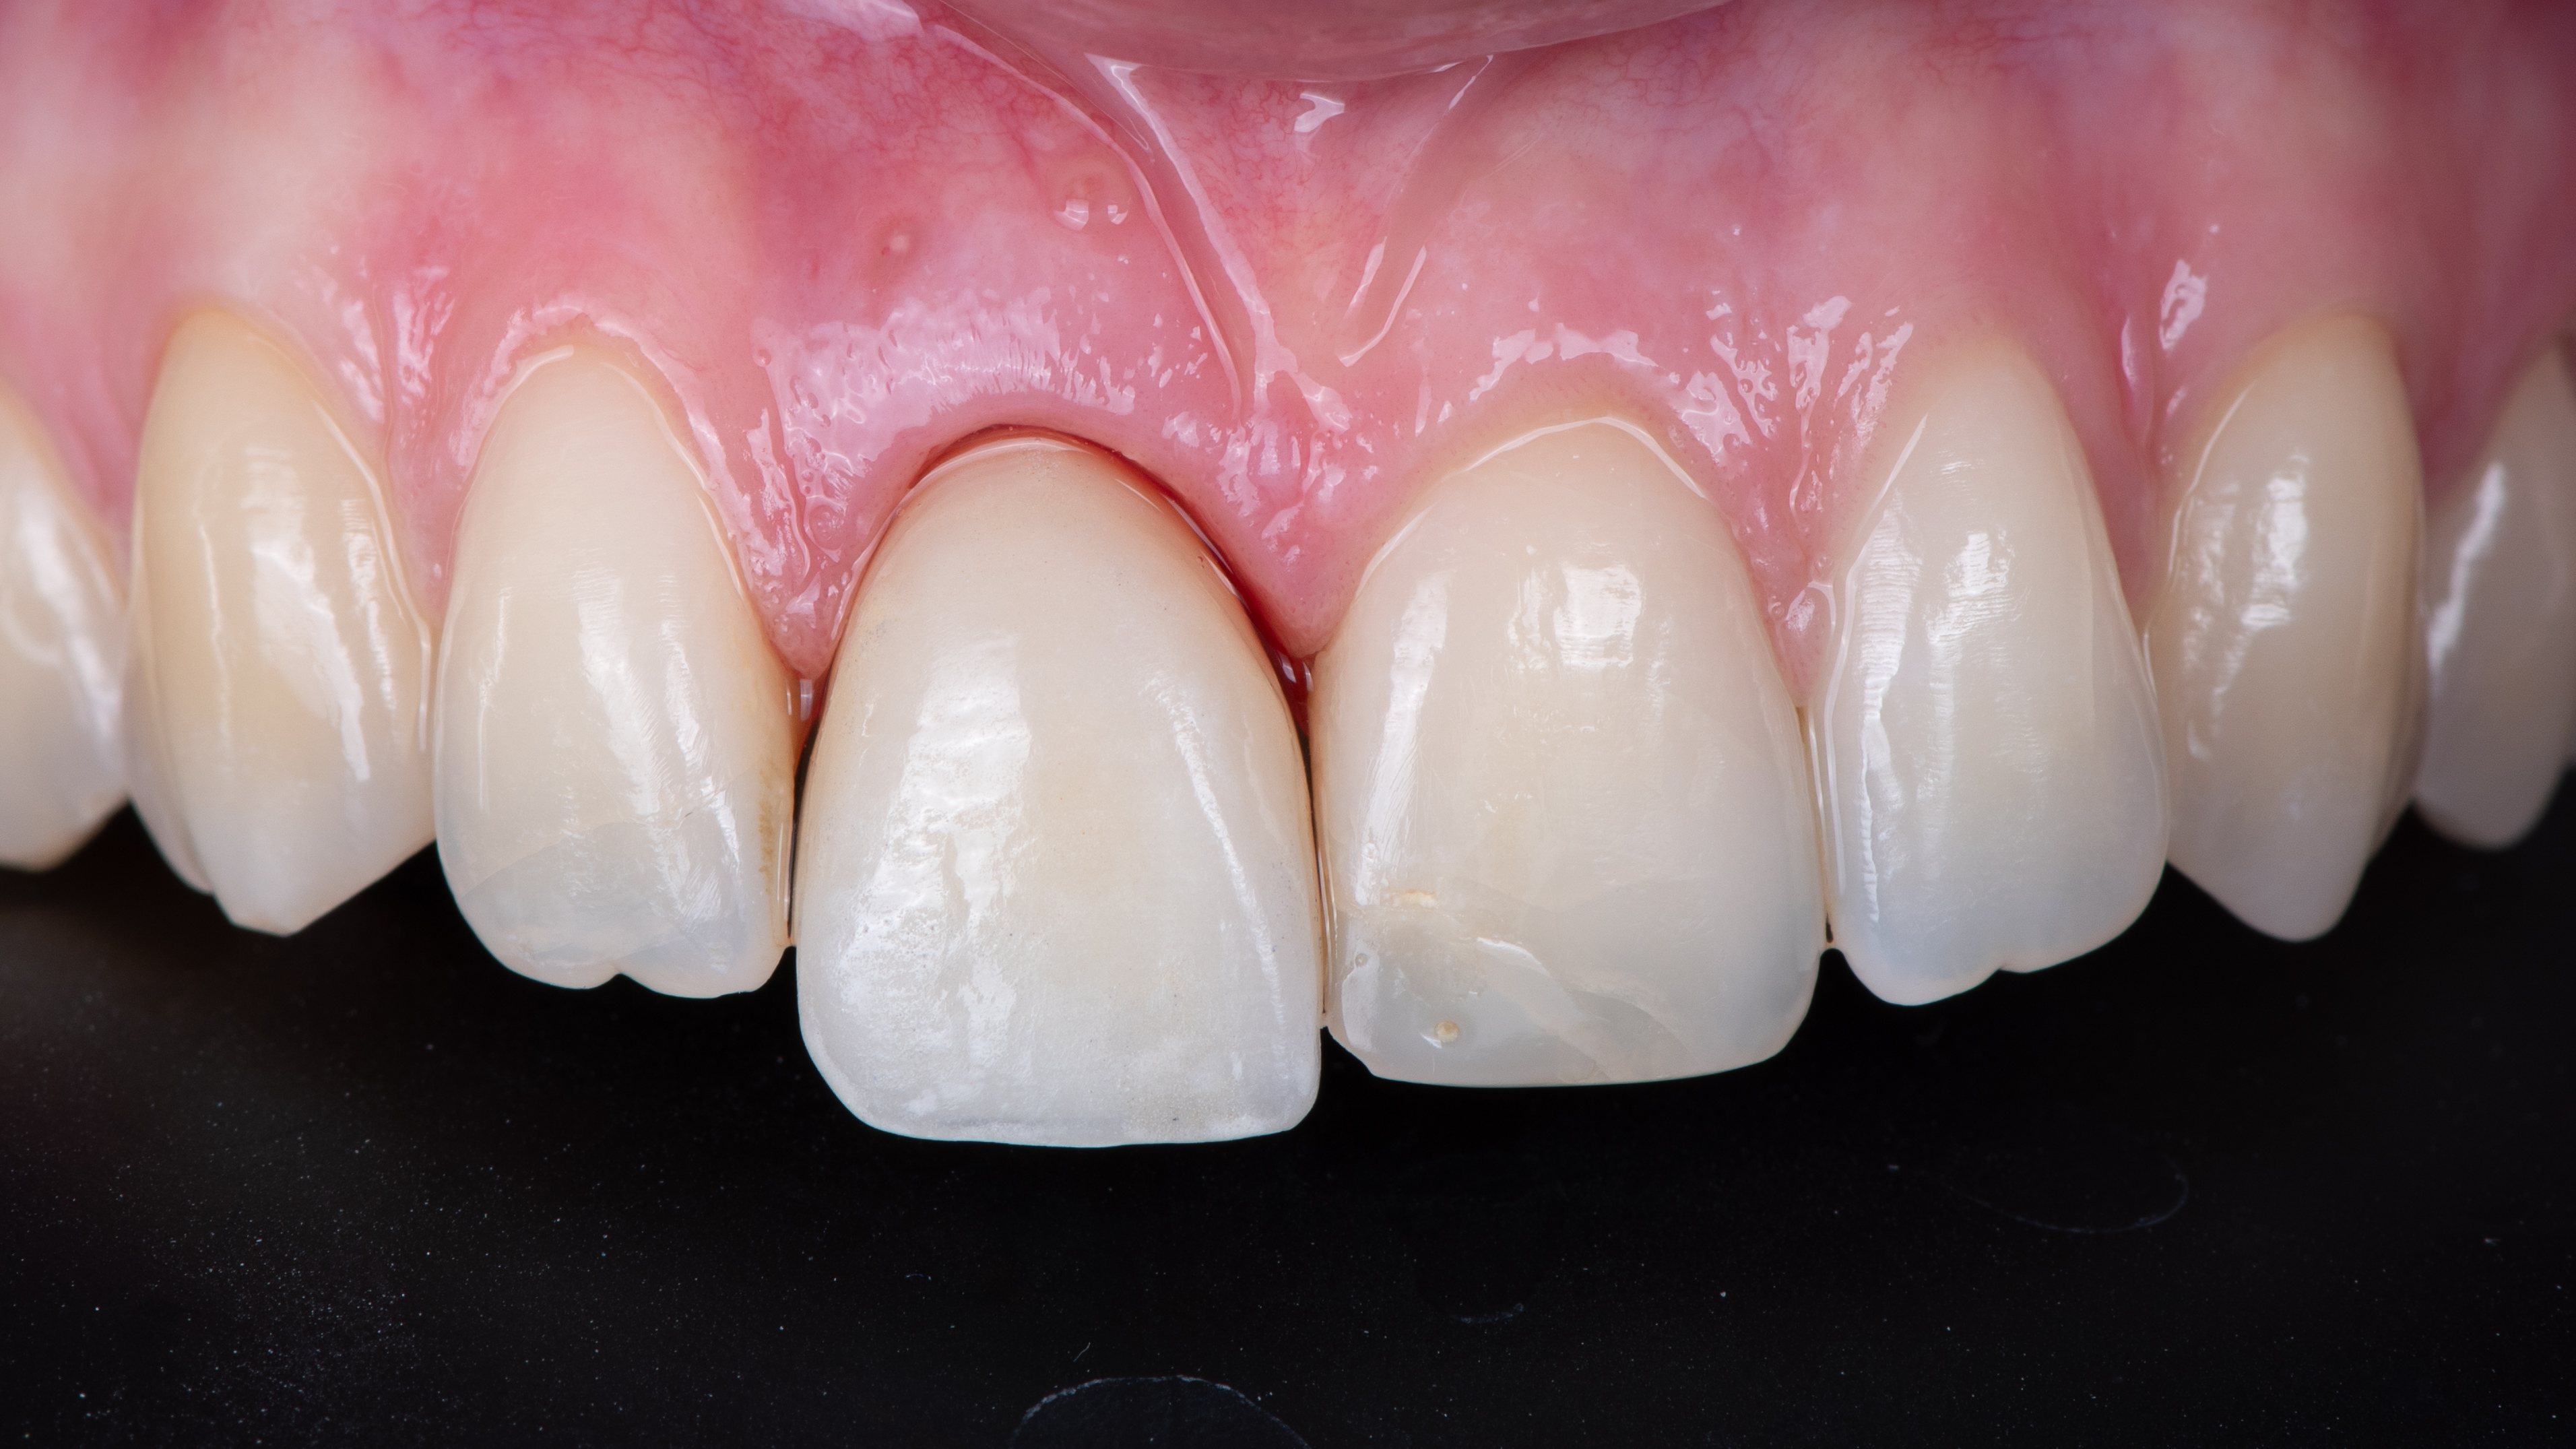

La patiente revient pour la pose de la prothèse d’usage. Nous réalisons donc un essayage de cette prothèse d’usage avant de réaliser le composite sur la dent 21.

Nous constatons que la cicatrisation est alors optimale et que la prothèse d’usage s’intègre parfaitement à son environnement (Photo 20).